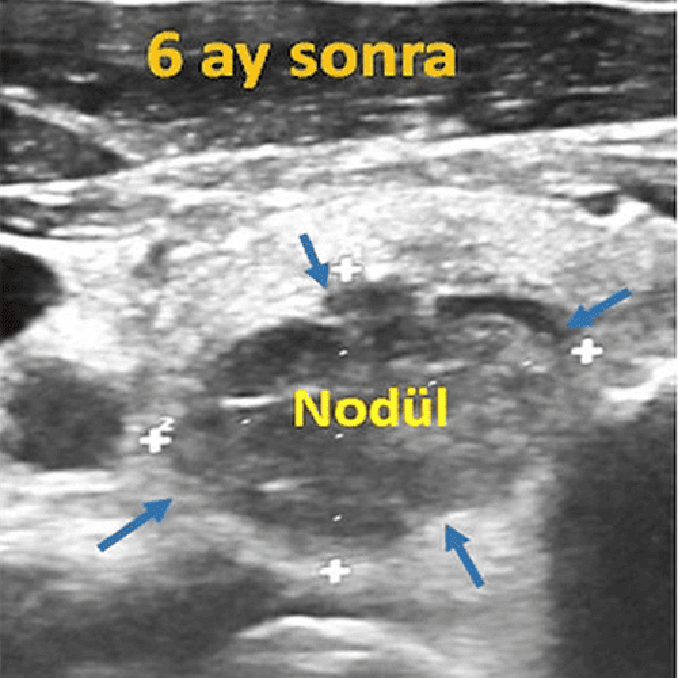

Sağ tiroid lobunda 57x50x49 mm boyutlarında solid nodülü olan hastamızda nodül ultrason eşliğinde perkütan radyofrekans ablasyonu ile tedavi edildi. Altı aylık ve 1 yıllık ultrason muayenelerinde nodülün hacimsel olarak sırasıyla %60 ve %90 oranında küçüldüğü saptanmıştır.

Tiroid nodülüne radyofrekans ablasyon tedavisi